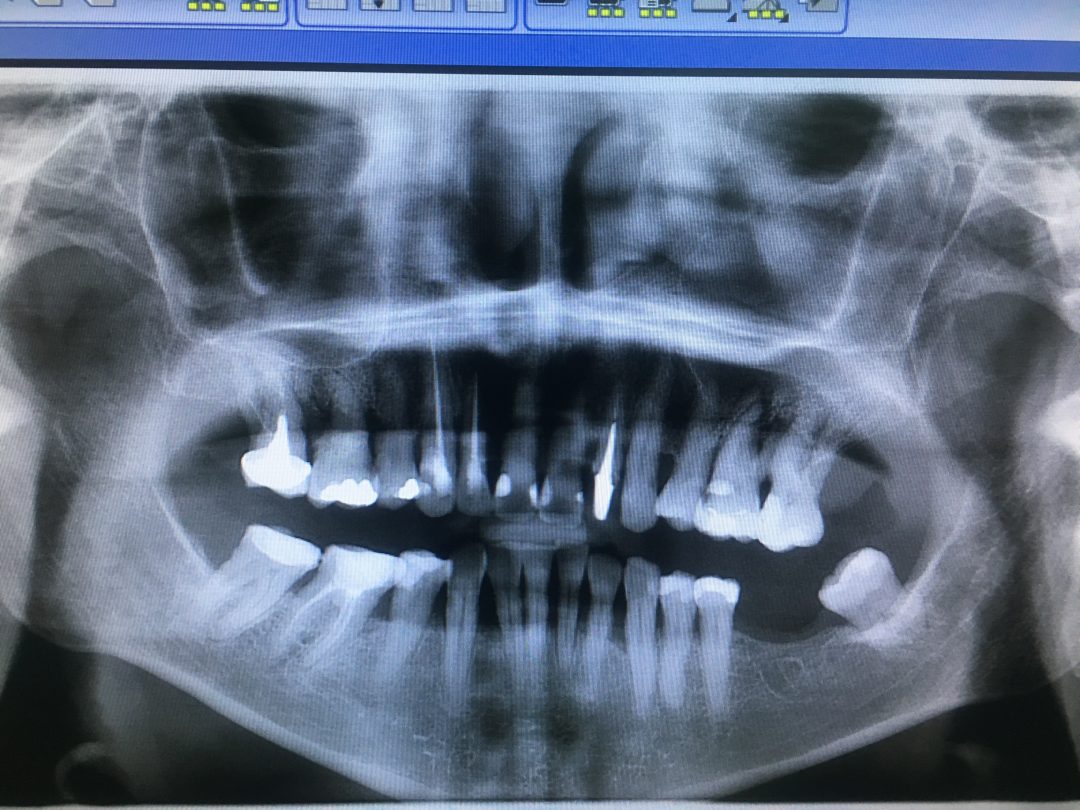

Технологические достижения: Planmeca и ОПТГ

Раздел: Образы вокруг